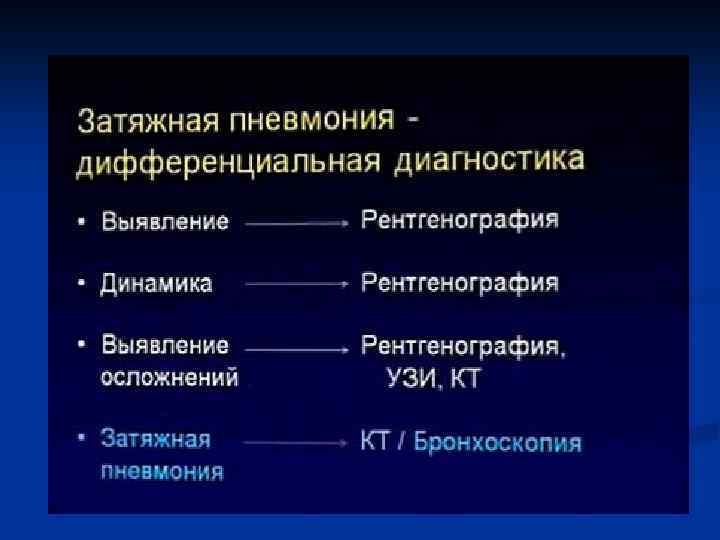

На I этапе обследования рентгенолог должен ответить на вопросы: Есть пневмония или нет 2. Локализация 3. Протяженность (если вся доля, то течение м. б. затяжное) 4. Характер пневмонии (долевой, ацинарный) 5. Первичная или вторичная На II этапе проследить изменения в динамике: 1. Рассасывание 2. Осложнения (нагноения, коллапсы) На III этапе (клинически выздоровление): 1. Полное ли рассасывание 2. Есть ли постпневмонические изменения легких (сетчатость, ячеистость) 1.

Показания к КТ грудной клетки n n n Недостаточная диагностическая информация стандартного рентгенологического исследования с наличием клиниколабораторных данных при подозрении на пневмонию Стертые клинические и лабораторные данные у больных с подозрением на пневмонию Затянувшийся кашель, субфебрилитет у больных с ОРВЗ Обострения хронических заболеваний бронхо-легочной системы Осложнения в процессе лечения больных пневмонией Затянувшиеся пневмонии